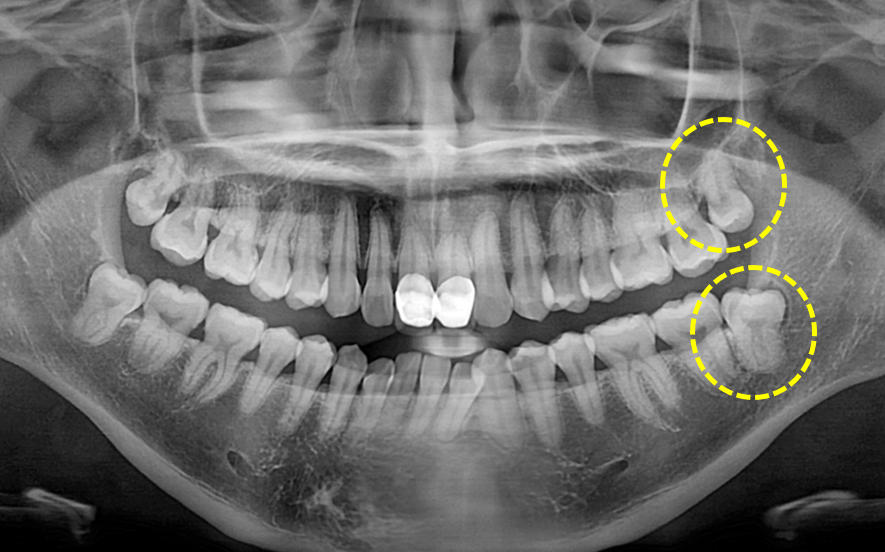

상, 하악 사랑니 발치

Before

발치 후 6개월 이상 지나게 되면 발치와가 치조골로 치유된 모습을 확인하실 수 있습니다.

위 케이스는 발치와가 완벽히 치유되어 그 전에 치아가 있었는지 조차 잘 모를 정도가 되었습니다.